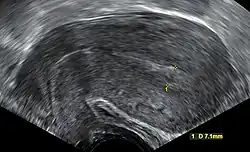

Transvaginal ultrasonography after an episode of heavy bleeding in an intrauterine pregnancy that had been confirmed by previous ultrasonography. There is some widening between the uterine walls, but no sign of any gestational sac, thus, in this case, being diagnostic of a complete miscarriage.

A complete miscarriage is when all products of conception have been expelled; these may include the trophoblast, chorionic villi, gestational sac, yolk sac, and fetal pole (embryo); or later in the pregnancy the foetus, umbilical cord, placenta, amniotic fluid, and amniotic membrane. The presence of a pregnancy test that is still positive, as well as an empty uterus upon transvaginal ultrasonography, does, however, fulfil the definition of pregnancy of unknown location. Therefore, there may be a need for follow-up pregnancy tests to ensure that there is no remaining pregnancy, including ectopic pregnancy.